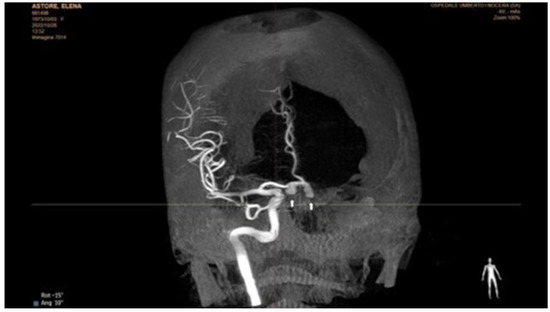

Chronic or Changeable Infarct Size after Spontaneous Coronary Artery Dissection

by Gordana Krljanac, Svetlana Apostolovic, Zlatko Mehmedbegovic, Olga Nedeljkovic-Arsenovic, Ruzica Maksimovic, Ivan Ilic, Aleksandra Djokovic, Lidija Savic, Ratko Lasica and Milika Asanin

Diagnostics 2023, 13(9), 1518; https://doi.org/10.3390/diagnostics13091518 - 23 Apr 2023

Spontaneous coronary artery dissection (SCAD) could be the cause of acute myocardial infarction (AMI) and sudden cardiac death. Clinical presentations can vary considerably, but the most common is the elevation of cardiac biomarkers associated with chest discomfort. Different pathological etiology in comparison with [...] Read more.

Spontaneous coronary artery dissection (SCAD) could be the cause of acute myocardial infarction (AMI) and sudden cardiac death. Clinical presentations can vary considerably, but the most common is the elevation of cardiac biomarkers associated with chest discomfort. Different pathological etiology in comparison with Type 1 AMI is the underlying infarct size in this population. A 42-year-old previously healthy woman presented with SCAD. Detailed diagnostical processing and treatment which were performed could not prevent myocardial injury. The catheterization laboratory was the initial place for the establishment of a diagnosis and proper management. The management process can be very fast and sometimes additional imaging methods are necessary. Finding predictors of SCAD recurrence is challenging, as well as predictors of the resulting infarct scar size. Patients with recurrent clinical symptoms of chest pain, ST elevation, and complication represent a special group of interest. Therapeutic approaches for SCAD range from the ”watch and wait” method to complete revascularization with the implantation of one or more stents or aortocoronary bypass grafting. The infarct size could be balanced through the correct therapeutical approach, and, proper multimodality imaging would be helpful in the assessment of infarct size. Full article